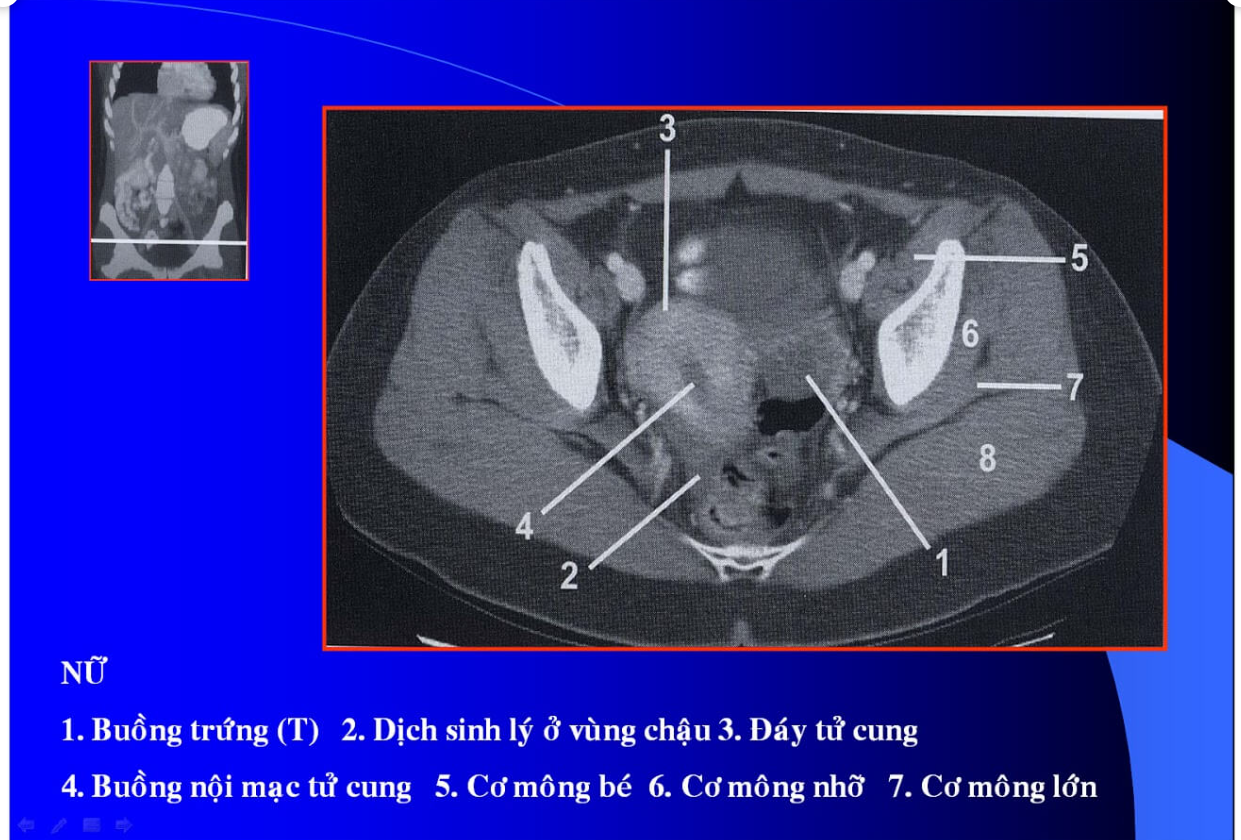

manh tràng? x cùng?